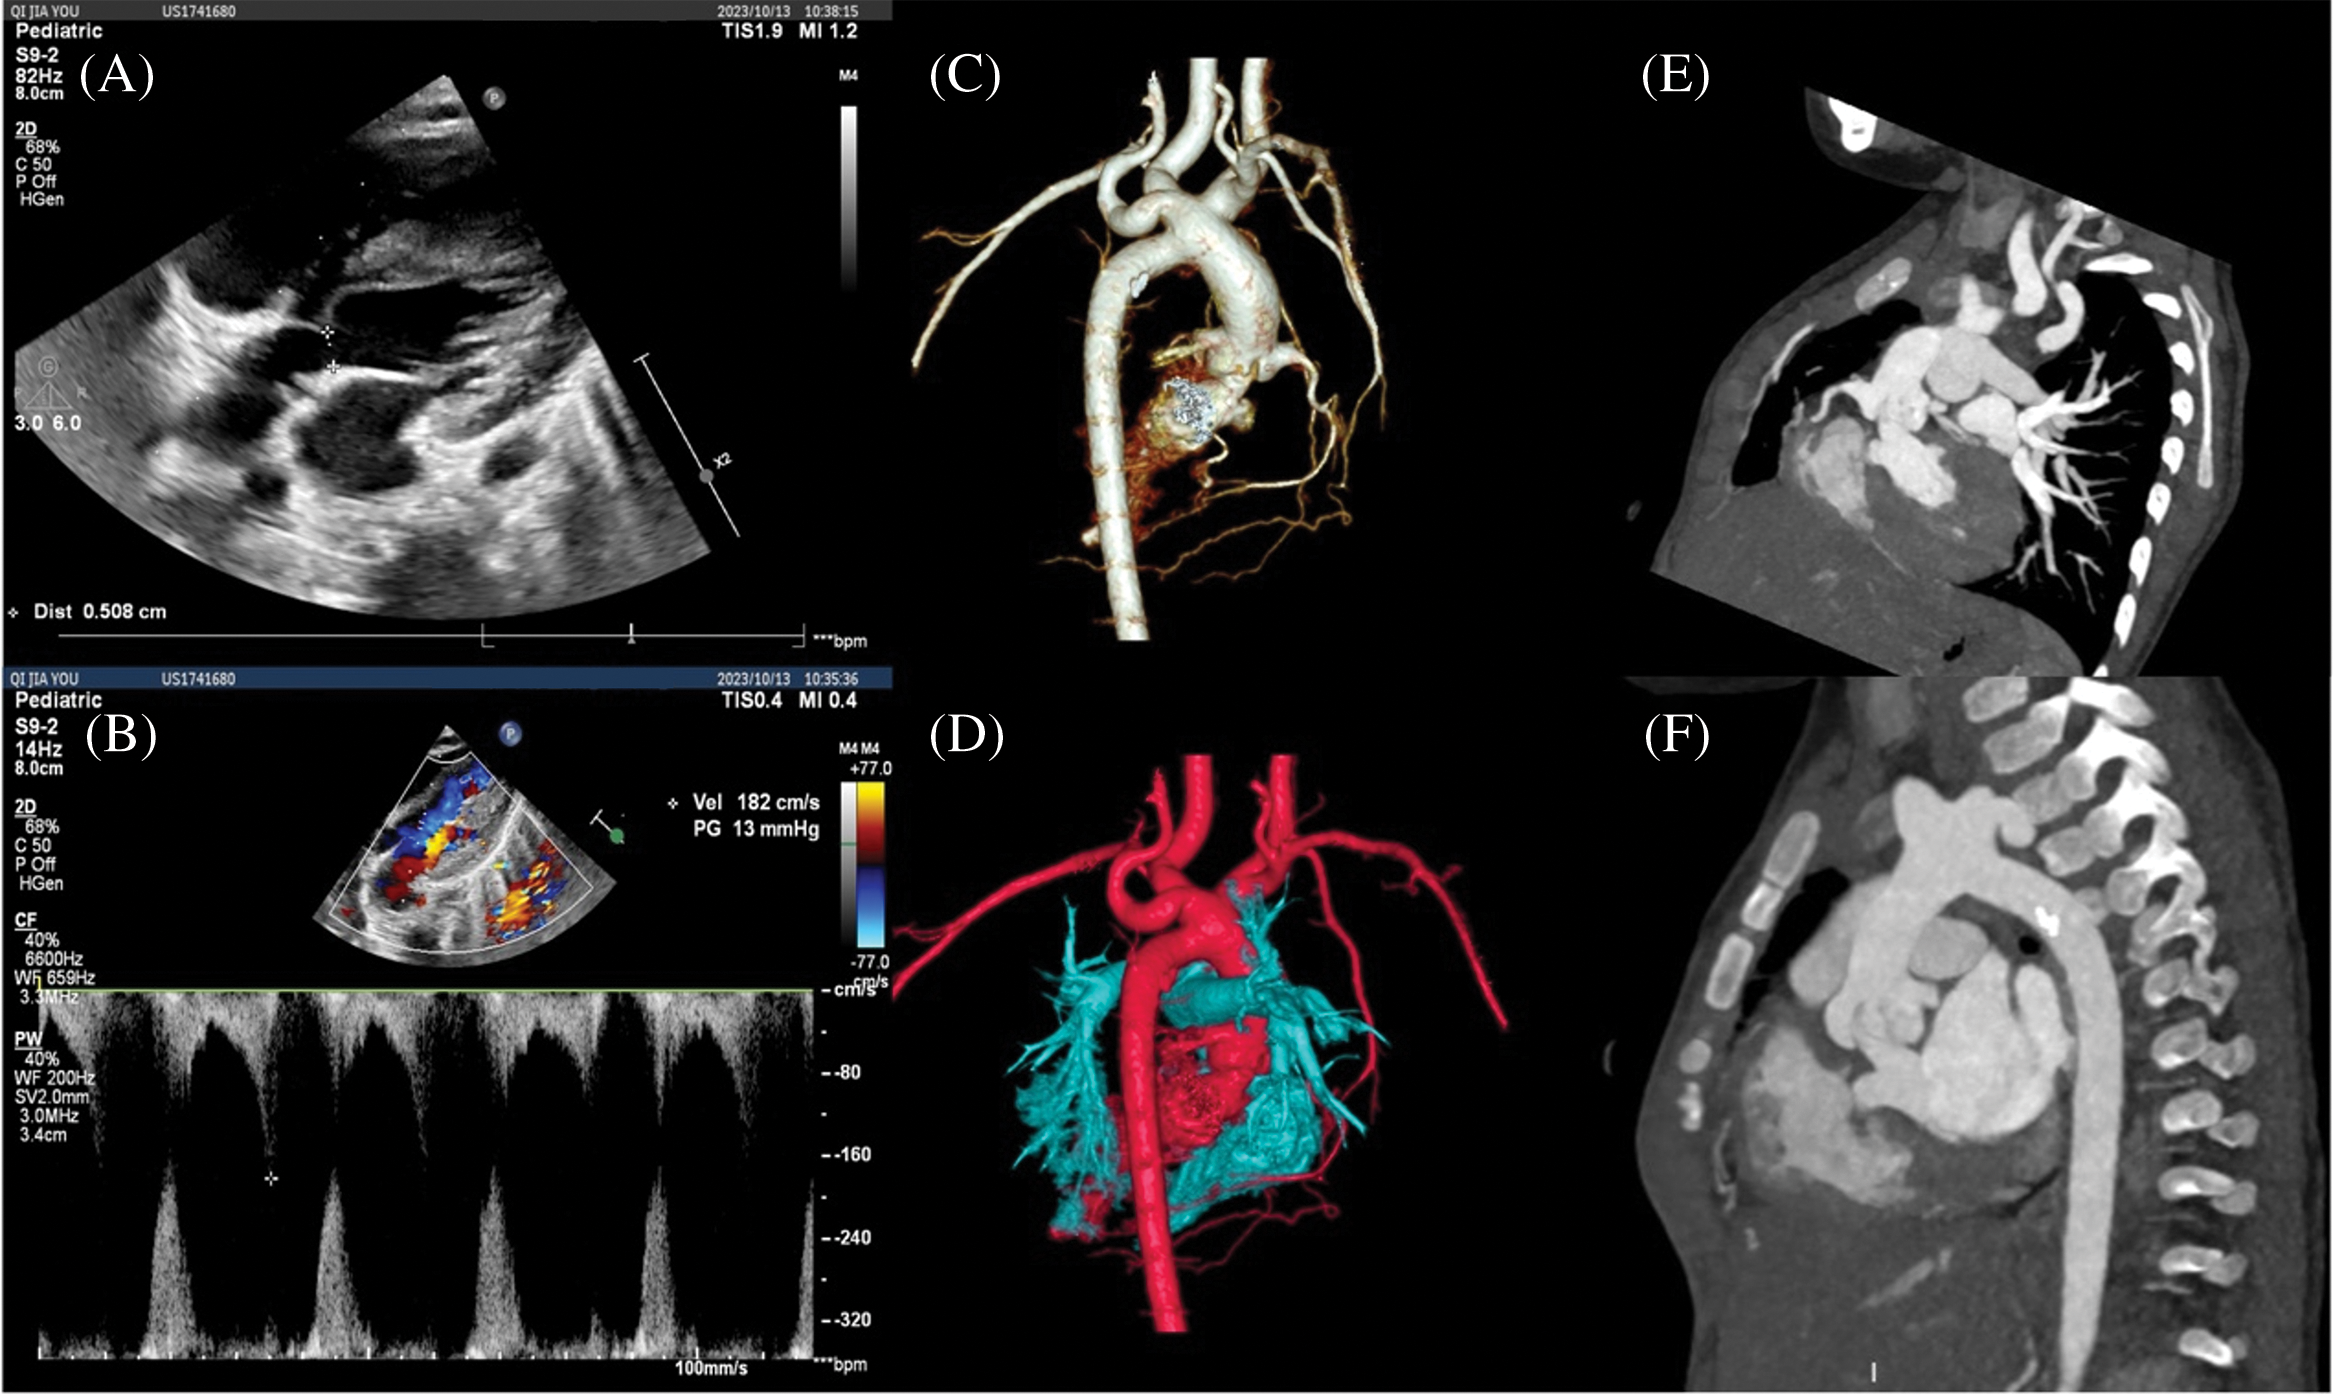

Figure 3: CTA images at 10 months after balloon valvuloplasty. (A, B) Echocardiography showed that the diameter of the aortic valve orifice was 5 mm, and the flow velocity at the beginning of the left ventricular outflow tract was 1.8 m/s; (C, D) Three-dimensional reconstruction of CTA showed that there was no obvious stenosis of the aortic arch and anastomosis after IAA correction; (E, F) Stenosis of the left ventricular outflow tract and aortic valve orifice, and dome-like changes